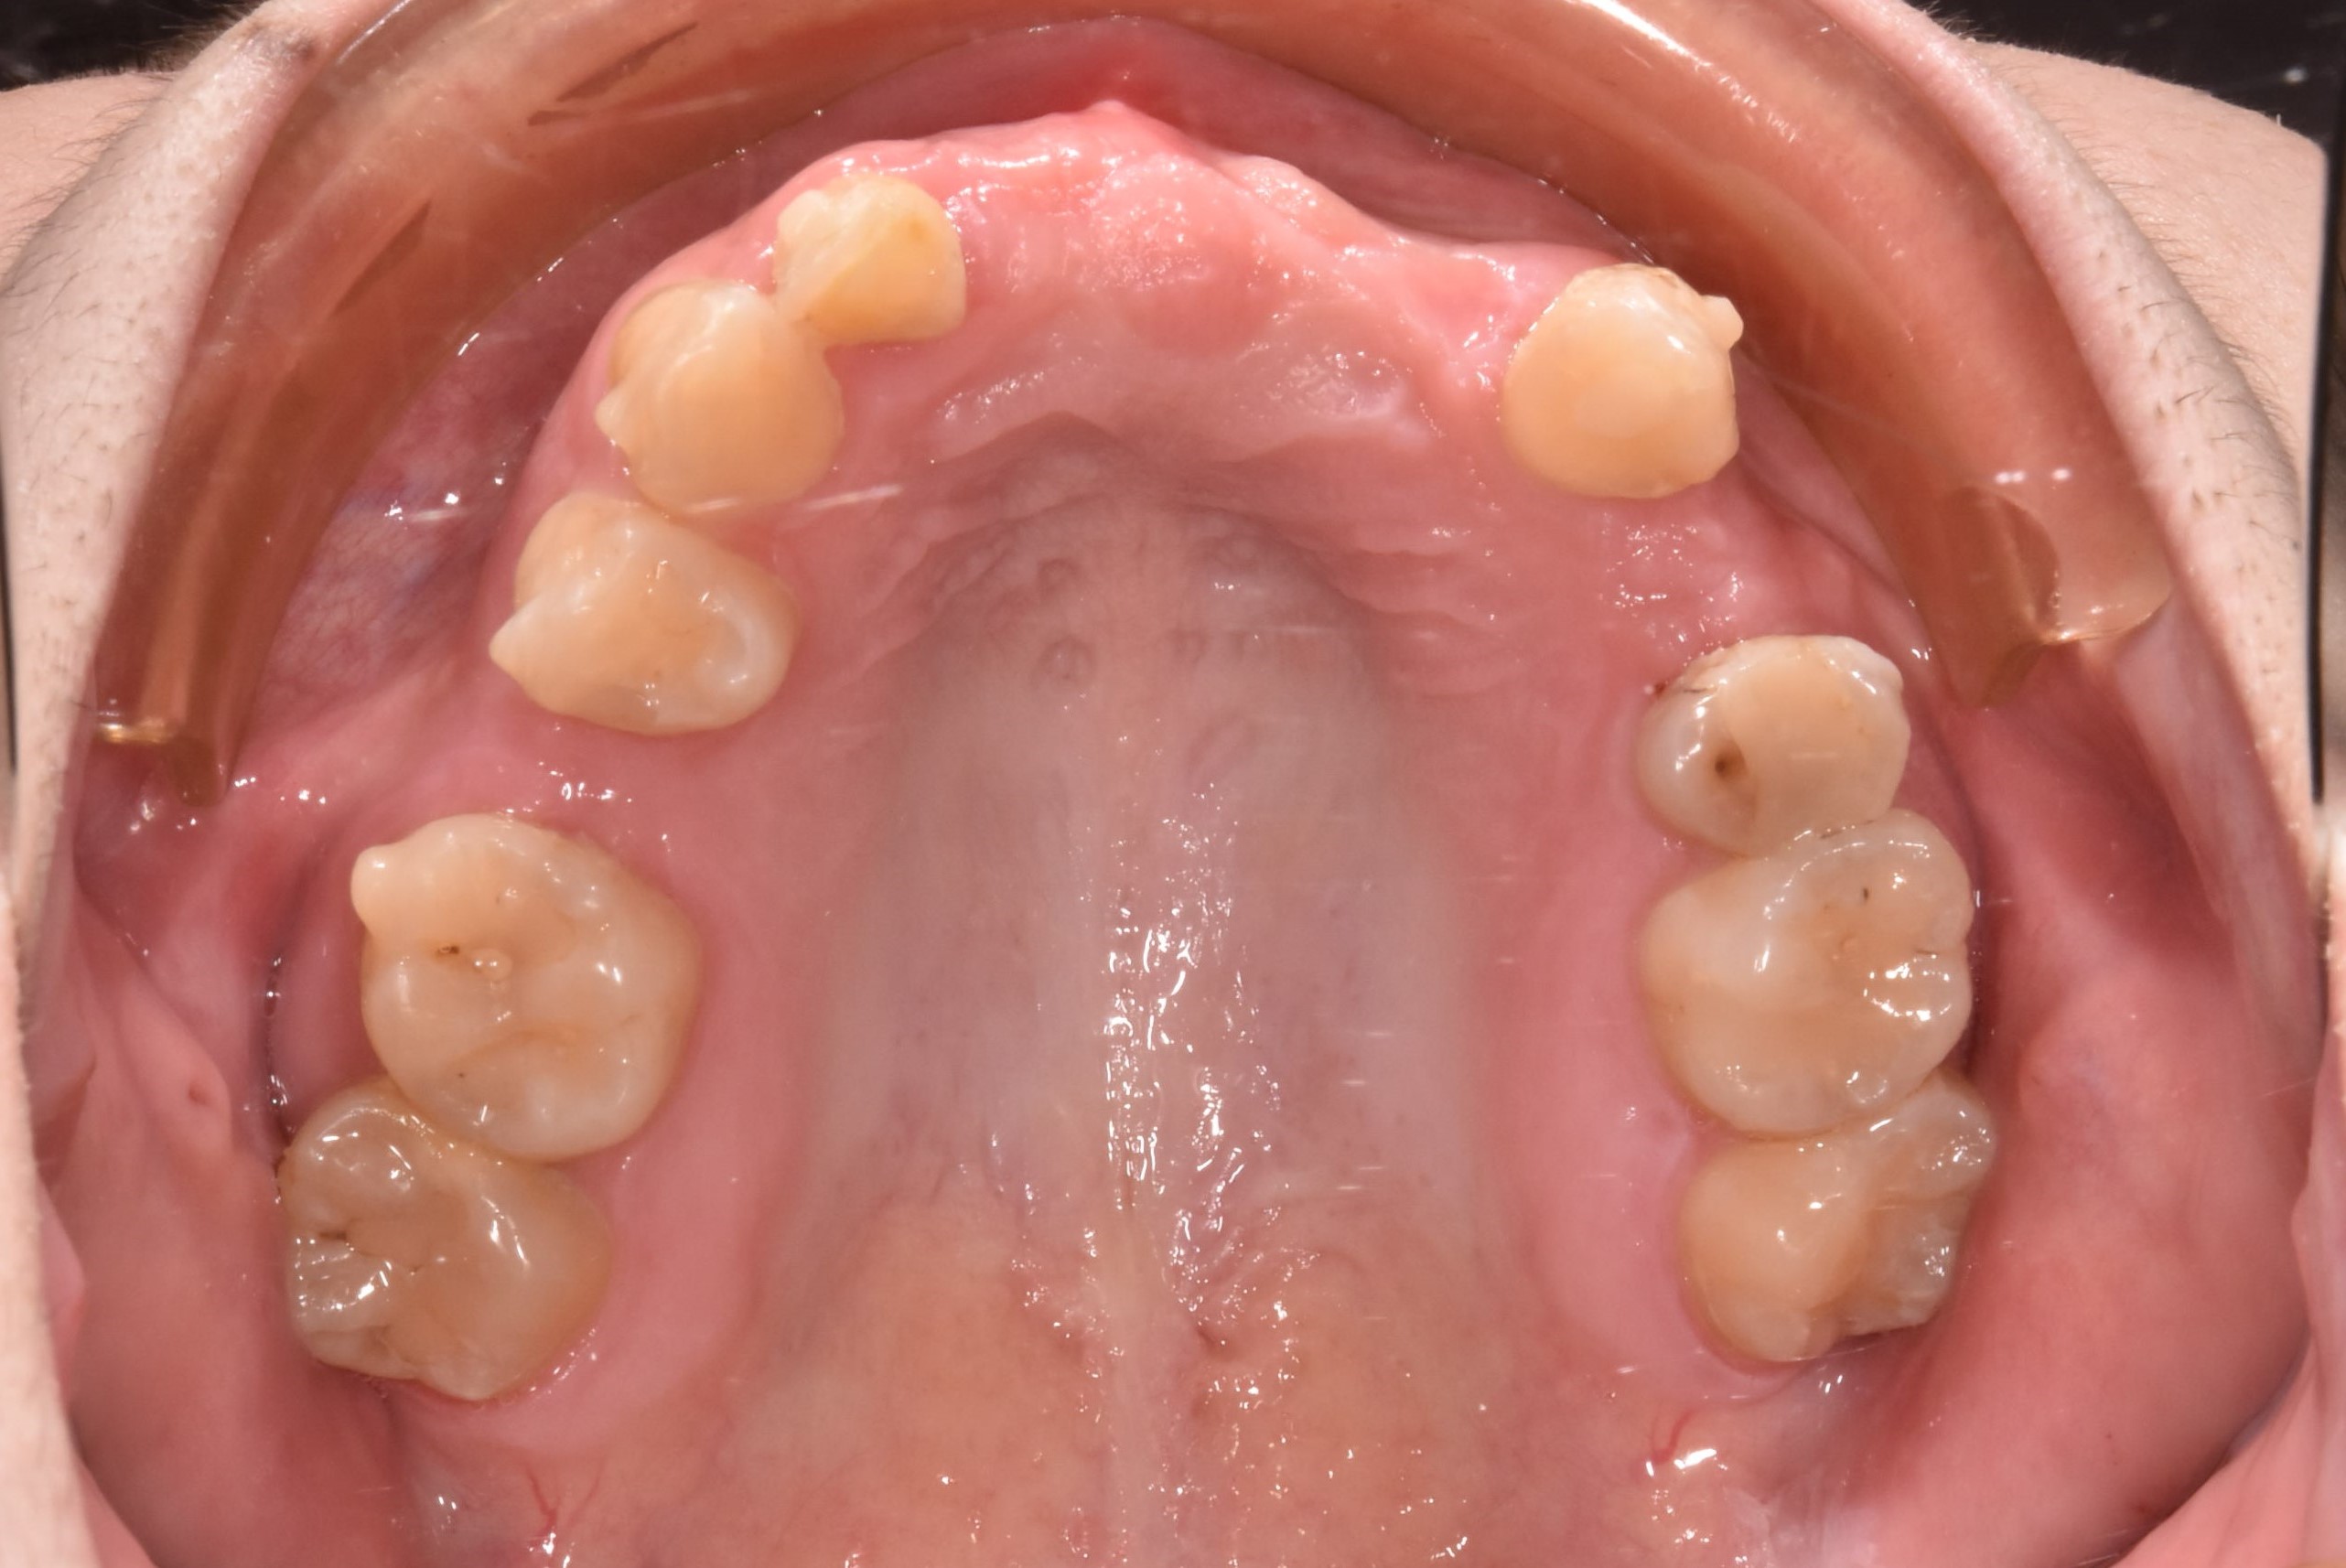

案例五

先把不好的牙根拔除,等待傷口癒合,進行補骨

翻瓣補骨的區域

補入所需骨粉

蓋上可吸收骨膜

*可吸收骨膜:會被身體自然吸收、不需再開刀取出的骨膜,用在補骨手術中,主要功能是隔離軟組織、保護骨粉、協助骨再生

最後縫合傷口,等待癒合